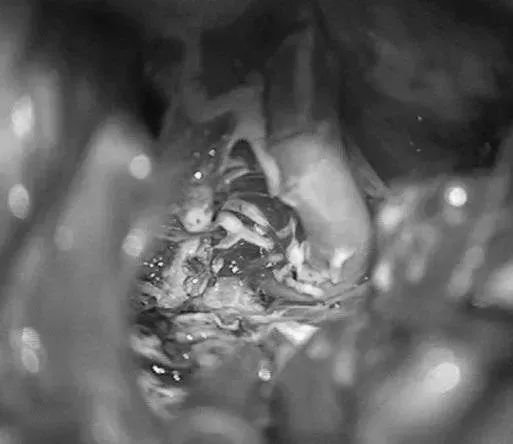

▼移除AVM

▼显露PCA周围至其ParOccA和CalcA(P2P)分叉

▼沿小脑幕见PCA的大脑脚段(P2A)和硬化的供血支。

- 第5步:这些供血支沿内侧软膜边缘(钩回)进入畸形团,形成内侧前界。

- 第6步:骨架化AChA和PCA的P2段,闭掉来自PCA的终末支,向内推移保护中脑穿支(PosThaP、PedP、CirP、ThGenP和mPChA)。通过岛叶和杏仁核界定的AVM的外侧缘,沿周边分离AVM,可以不影响记忆功能。

- 第7步:巨大的AVM会向颞下角延伸,必须打开脑室才能确认其外侧边界。这样的垂直入路会遮挡AVM后上缘,要把它向内下拉入手术通道里。与BVR相连的畸形团位置深在,直到分离快结束的时候才能看到。